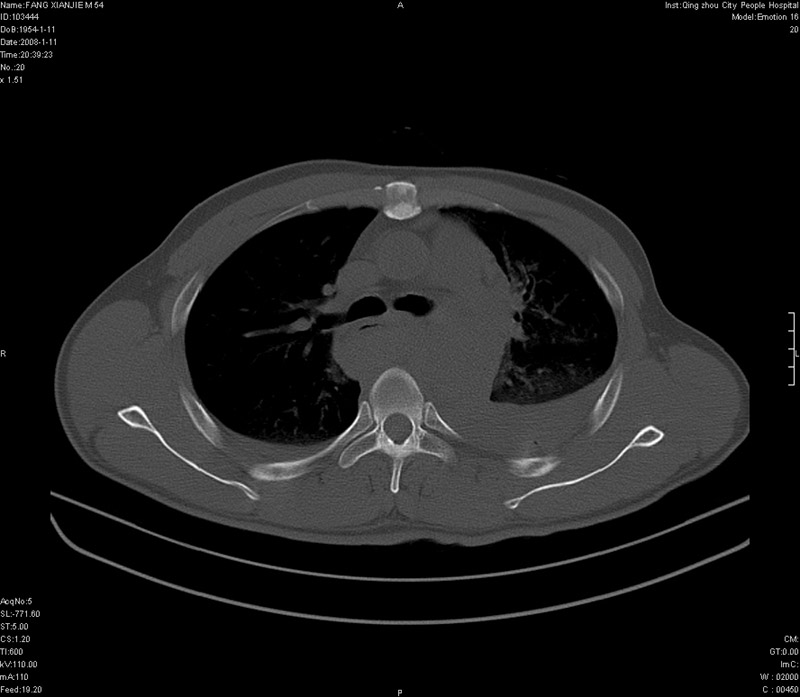

男性,40岁。胸部被车压伤伴胸痛1小时来院就诊。检查:一般情况尚可,血压110/80,胸部及上腹部压痛。结果在三天后公布。骨窗在横断位、冠矢状显示肋骨、胸椎、和胸骨未见骨折征象。

这个片子诊断起来确实很难呀!!病人病史一般情况尚可,血压110/80,如果是战友们所说的主动脉破裂的话,这个病史好像不太支持!!现在看有纵隔积液及血胸,食管增粗并有上段积气的表现,是不是可以考虑食管破裂或者膈肌撕裂并形成食管裂孔疝的可能。至于主动脉破裂并形成假性动脉瘤的可能好像很罕见,实在不敢妄加猜测!!这个片子一定不错,不希望一定正确,但很期待结果!!

ct11308:胸部外伤1小时(证实病例) (2008-1-13 16:2)结果如下:病人入院后两小时后症状加重,8小时后在征得病人家属同意做了ct增强扫描。如下图。最终临床诊断:外伤性胸主动脉破裂并纵隔内血肿。由于有运动性伪影,胸骨在矢状面重建的图像似有骨折征,这是一种假象,我们称之为“假骨折”,这在多层ct重建中经常性遇到,必要时要结合横断图像鉴别之。现在,病人的一般情况较差,是否要手术家属尚有争议,如果手术修补,难度较大,需要专门预定制作固定支架。

当然,对于该病例,其它非重要的诊断还有:右侧少量气胸;左侧胸腔积液;左侧轻度肺挫裂伤。对于纵隔内血肿,我们曾经遇到过多例,也有怀疑主动脉的破裂,但是,均未得到具体出血部位的明确诊断。